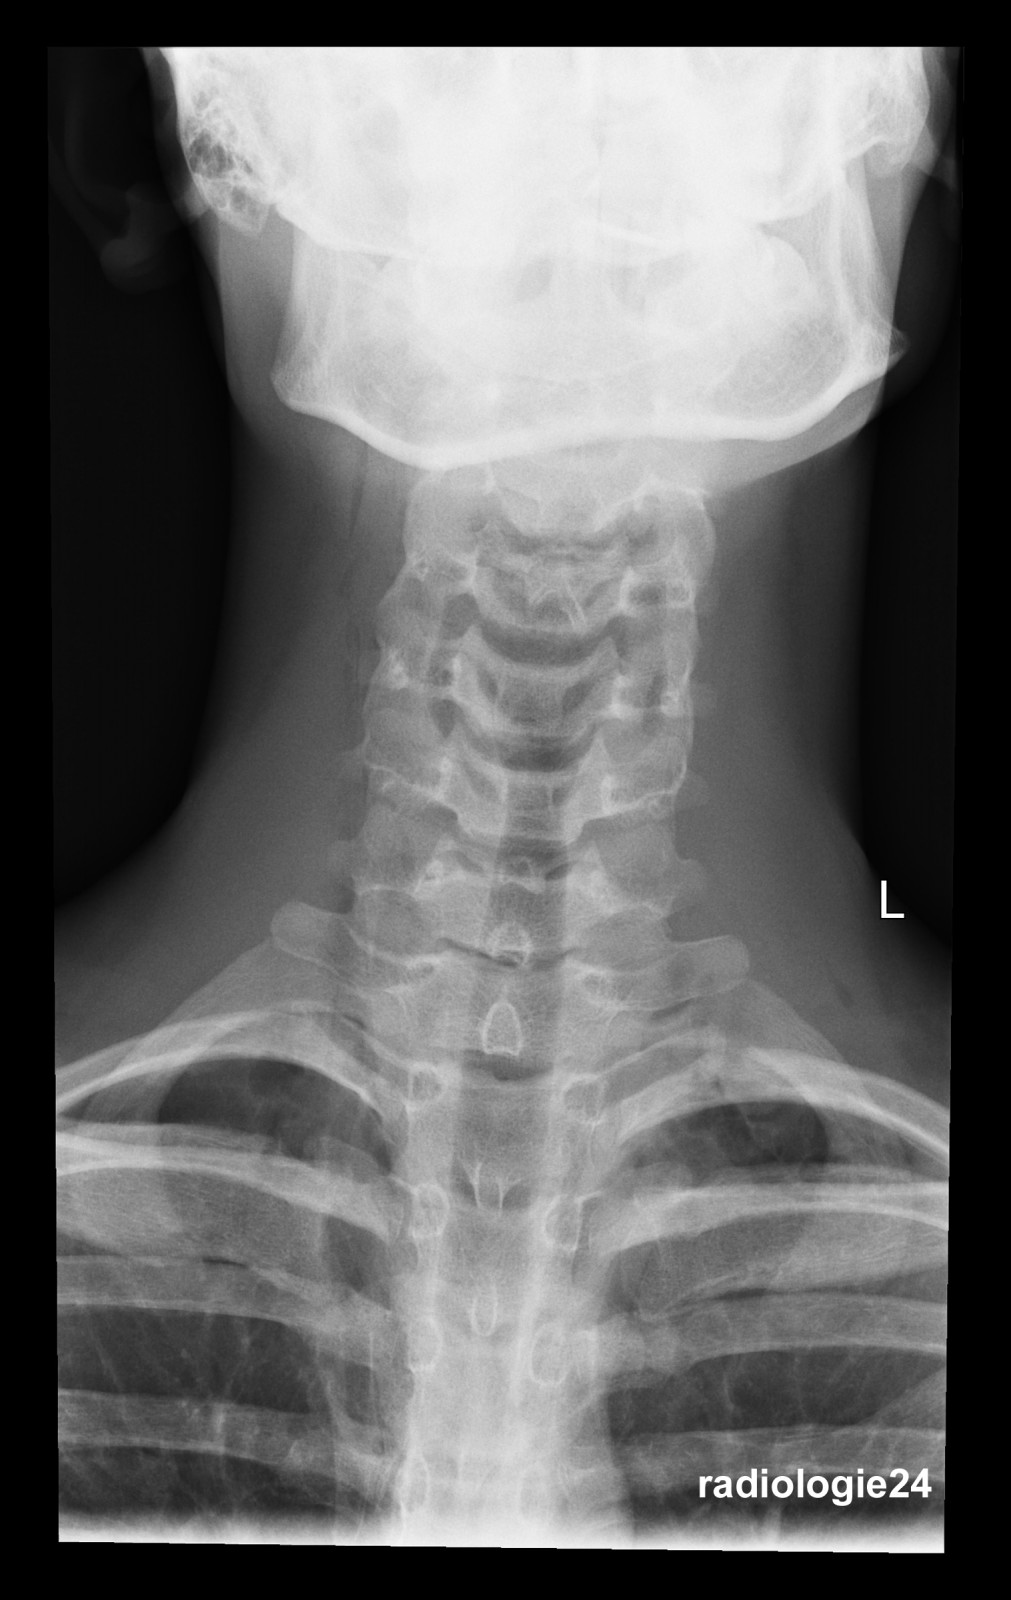

Röntgenfall des Monats Januar 2018 mit Auflösung

17 jähriger Patient Sturz auf den Rücken beim Crossbiken. Schmerzen HWS und Thorax. Fraktur, Pneumothorax, andere Pathologien? Weitere bildgebende Diagnostik? Welche? Warum?